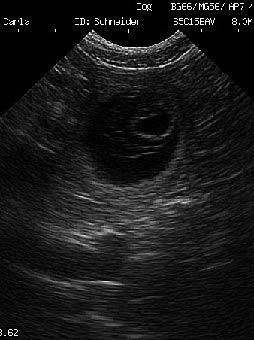

Schon zwei Wochen vor dem Geburtstermin hat Carla mit den Bauarbeiten für ihre Wurfhöhle begonnen. Sie hat ein Beet direkt auf unserer Terasse als Geburtsort auserkoren und will nun jede Nacht raus, um die Bauarbeiten fortzusetzen. |